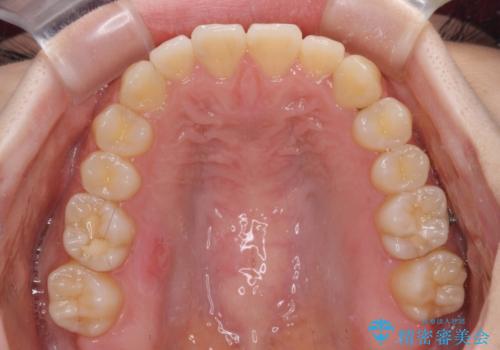

前歯のクロスバイト インビザラインによる矯正治療

- 前歯のクロスバイトとデコボコを気にして来院された患者様です。

骨格的に下顎前突傾向であるため、自己管理が煩わしくないようであれば、インビザラインによる矯正治療がお勧めとなります。

インビザラインを用い、下顎歯列を後方に移動させながら全市の被蓋を改善し、歯並びを整えていくこととしました。

途中マウスピースが使用できず、来院されない期間があり、治療期間は長くかかりましたが、無事に治療を終えることができました。